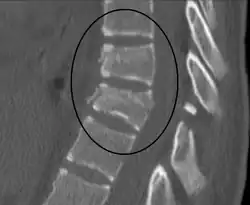

| A Chance fracture of T10 and fracture of T9 due to a seatbelt during an MVC. | |